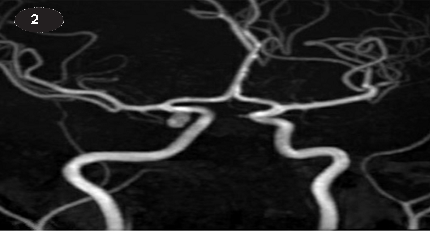

Chẩn đoán hình ảnh: Bao gồm chụp cắt lớp vi tính mạch máu (CTA), chụp cộng hưởng từ (MRI), chụp mạch cộng hưởng từ (MRA) hoặc chụp mạch xóa nền kỹ thuật số (DSA).

Trong khi DSA là tiêu chuẩn vàng vì nó có thể phát hiện chứng phình động mạch dưới 3 mm nhưng DSA gây đột quỵ khoảng 1% và hiện nay hiếm khi được sử dụng cho mục đích chẩn đoán. So với DSA, CTA nhanh hơn, ít tốn kém hơn, ít xâm lấn hơn và an toàn hơn. CTA cũng sử dụng ít độ tương phản hơn DSA. CTA cũng được ưu tiên hơn MRI để quét nhanh hơn và giảm hiện tượng chuyển động. Đây cũng là loại hình ảnh được ưa thích đối với những bệnh nhân mắc chứng sợ bị vây kín hoặc những người có bộ phận cấy ghép kim loại không tương thích. Vì MRA có thể được thực hiện mà không cần dùng thuốc cản quang và bức xạ nên phương pháp này được ưa chuộng hơn ở bệnh nhân suy thận và trẻ nhỏ. MRI/MRA có độ tương phản có độ phân giải cao hơn đối với các tổn thương không phình mạch.

Cả CTA và MRA đều có thể phát hiện chứng phình động mạch nhỏ tới 4mm, nhưng CTA có thể có độ phân giải và độ nhạy cao hơn. Phát hiện chứng phình động mạch PCommA < 5 mm bằng CTA có độ nhạy lên tới 99,4-99,8% và độ đặc hiệu lên tới 99,1-99,6%. Việc phát hiện chứng phình động mạch ở bất kỳ kích thước nào bằng MRA có độ nhạy tổng thể là 95% và độ đặc hiệu là 89%.

HÌNH ẢNH CHỤP CỘNG HƯỞNG TỪ

Phình động mạch thông sau PCCommA bên phải , KT: 6x3.8x3.6 mm